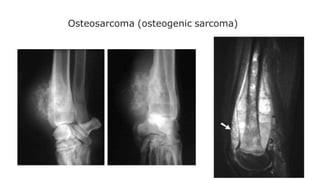

Osteosarcoma (osteogenic sarcoma)

Occurs mainly in the 5–20-year-old age group, but is

also seen in the elderly following malignant change in

Paget’s disease.

The tumour often arises in a metaphysis, most

commonly around the knee.

Florid spiculated periosteal reaction is present, the so-

called sunray appearance

The tumourmay elevate the periosteum to form a

Codman’s triangle